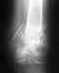

Добрый день! Очень нужна консультация специалиста травматолога После аварии у меня 1) - справа многооскольчатый перелом пяточной кости со смещением отломков, перелом ладьевидной кости. 2) слева- оскольчатый перелом передних отделов пяточной кости, таранной кости сосмещением. Что делать? Какие современные методы оперативного операционного вмешательства мне необходимы? Жду помощи. Больше надеяться не на кого. Как говорится помоги себе сам.

02/01/2012 года в 12.45 поппал в аварию. Доставлег в ЦГБ в 13 часов. Травму обнаружили только в 17 часов, после того, как начали опухать ноги. Переломы закрытые. В настоящее время лечу инфицированные раны, которые получились в связи с с тем, что не правильно наложили гипс- перетянули. В данный момент модрали кожу с ног и делают перевязки. Это продолжается уже с 10.01.2012г. Сегодя,16.01.2012г мне делают повторные снимки ног без гипса. Готовят к операции. ЭЖду От Вас дальнейших рекомендаций. С ув,Морозов.